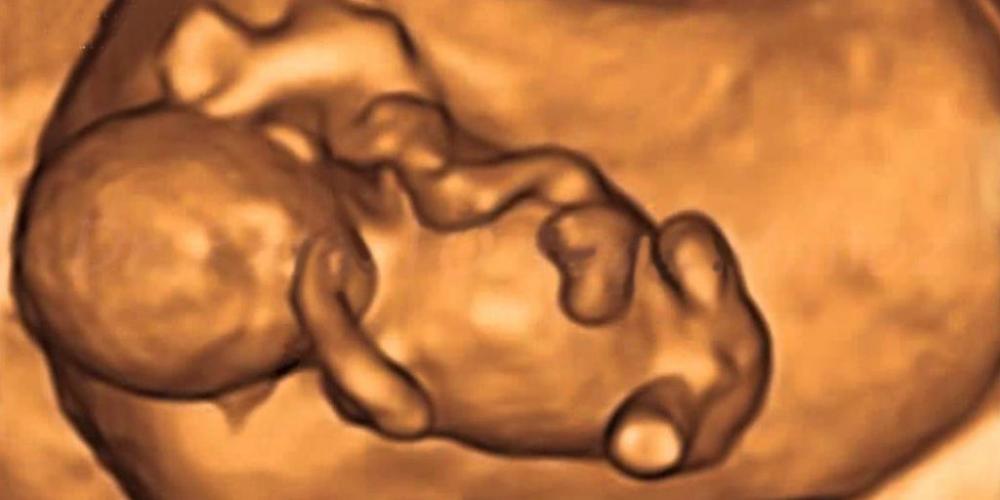

EL ESTADO MATÓ A 98 NIÑOS ARGENTINOS POR DÍA EN 2021

En los primeros 11 meses de este año, el Estado mató a 32.758 argentinos indefensos, inocentes, débiles, necesitados de protección, sin salida, acorralados, en condiciones de crecer y desarrollarse, de recibir y dar...